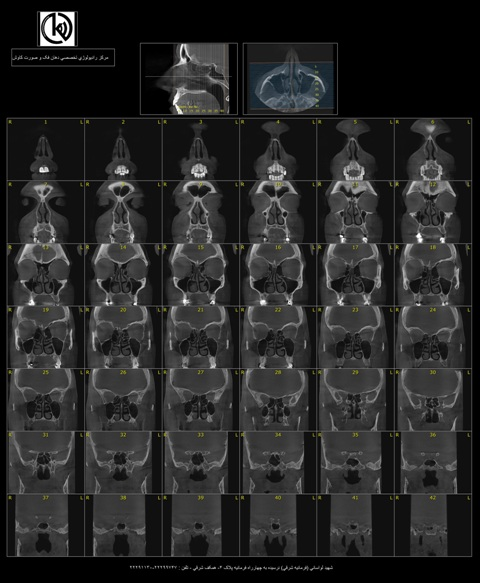

اسکن سه بعدی یا سی تی اسکن فک و دندان

هنگامی که دندانپزشک شما درمان ایمپلنت دندانی را برایتان درنظر گرفته باشد ، برای بررسی ابعاد استخوانی و آناتومی ناحیه مور...

ادامه مطلب